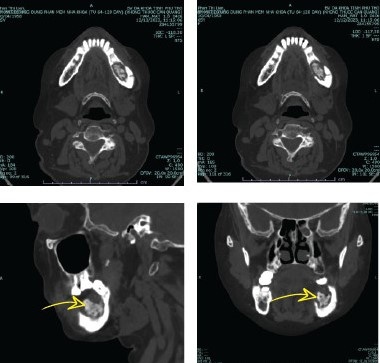

Kết quả chụp CT cho thấy bà bị viêm hoại tử xương hàm dưới bên trái trên nền bệnh đái tháo đường. Vị trí răng đã nhổ vẫn còn mảnh xương chết chưa được lấy hết.

Ảnh chụp CT cho thấy bệnh nhân vẫn còn mảnh xương hết chưa được lấy hết ở vị trí nhổ răng. Ảnh: BVCC.